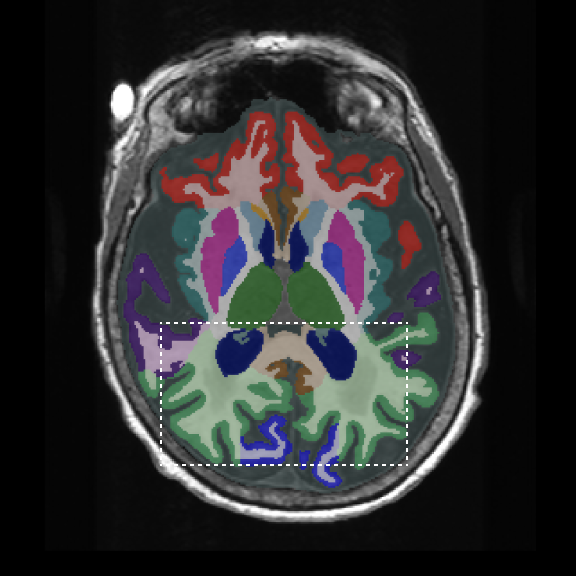

Retrospective brain volumetric analysis in a female patient diagnosed with Alzheimer’s disease at age 77 showed progressive brain atrophy over a 5-year period. The scans demonstrate temporal cortical atrophy with marked ex-vacuo enlargement of the lateral ventricles.

PATIENT

Female patient diagnosed with Alzheimer's Disease at Age 77

Analysis period

5 years

regions of interest

Temporal cortex

Hippocampus

Inferior lateral ventricles

Age 72

Age 74

Age 77

Lateral ventricle